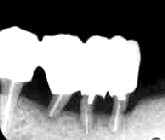

図1-l 再手術直後  '95年3月16日 Fop+Nd:YAGレーザー(根面処理) |

図1-m 再手術後3か月  '95年6月14日 歯槽骨の再生が認められる |

図1-n 再手術後1年  '96年3月27日 歯槽硬線が出現し骨の緻密化を確認 |